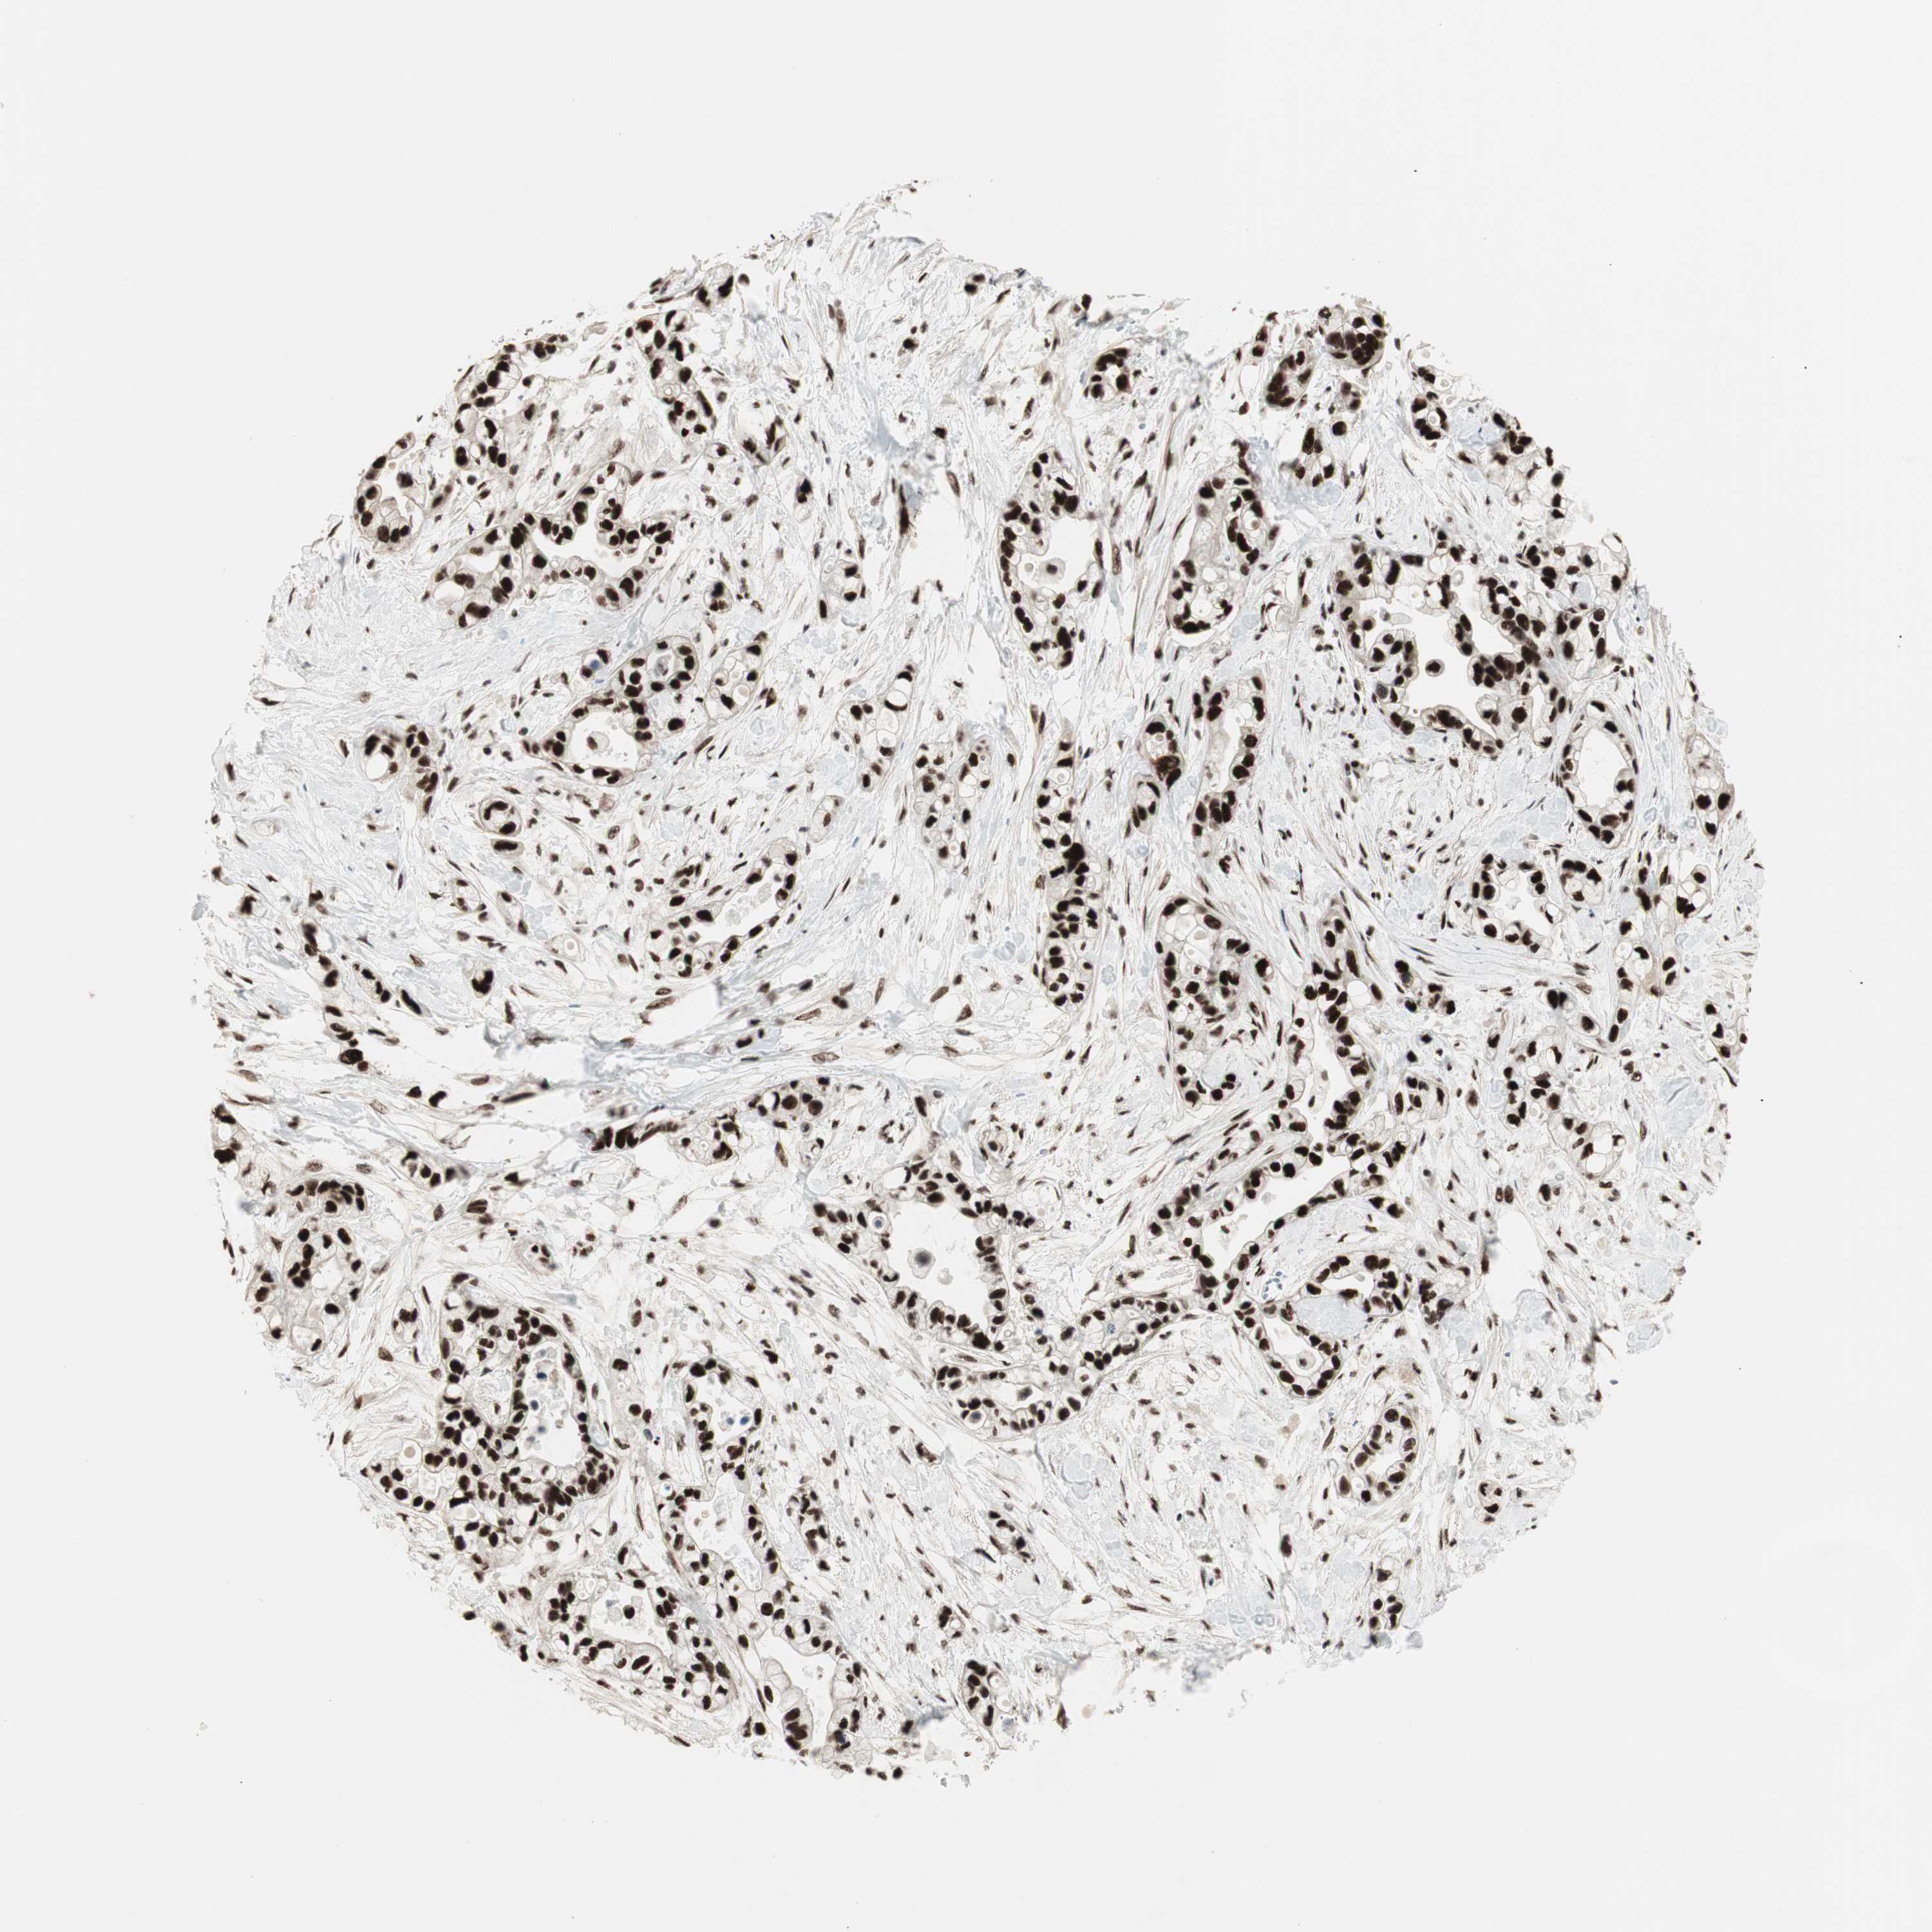

PANCREATIC CANCER - Protein expressioni

A mouse-over function shows sample information and annotation data. Click on an image to view it in a full screen mode. Samples can be filtered based on level of antibody staining by selecting one or several of the following categories: high, medium, low and not detected. The assay and annotation is described here.

Note that samples used for immunohistochemistry by the Human Protein Atlas do not correspond to samples in the TCGA dataset.

Antibody stainingi

Antibody staining in the annotated cell types in the current human tissue is reported as not detected, low, medium, or high, based on conventional immunohistochemistry profiling in selected tissues. This score is based on the combination of the staining intensity and fraction of stained cells.

Each image is clickable and will lead to virtual microscopy that enables deeper exploration of all samples and also displays staining intensity scores, fraction scores and subcellular localization as well as patient and tissue information for each sample.

Antibody HPA008926

Antibody CAB011625

Staining

High

Medium

Low

Not detected

Intensity

Strong

Moderate

Weak

Negative

Quantity

>75%

75%-25%

<25%

None

Location

Nuclear

Cytoplasmic/membranous

Cytoplasmic/membranous,nuclear

Adenocarcinoma, NOS